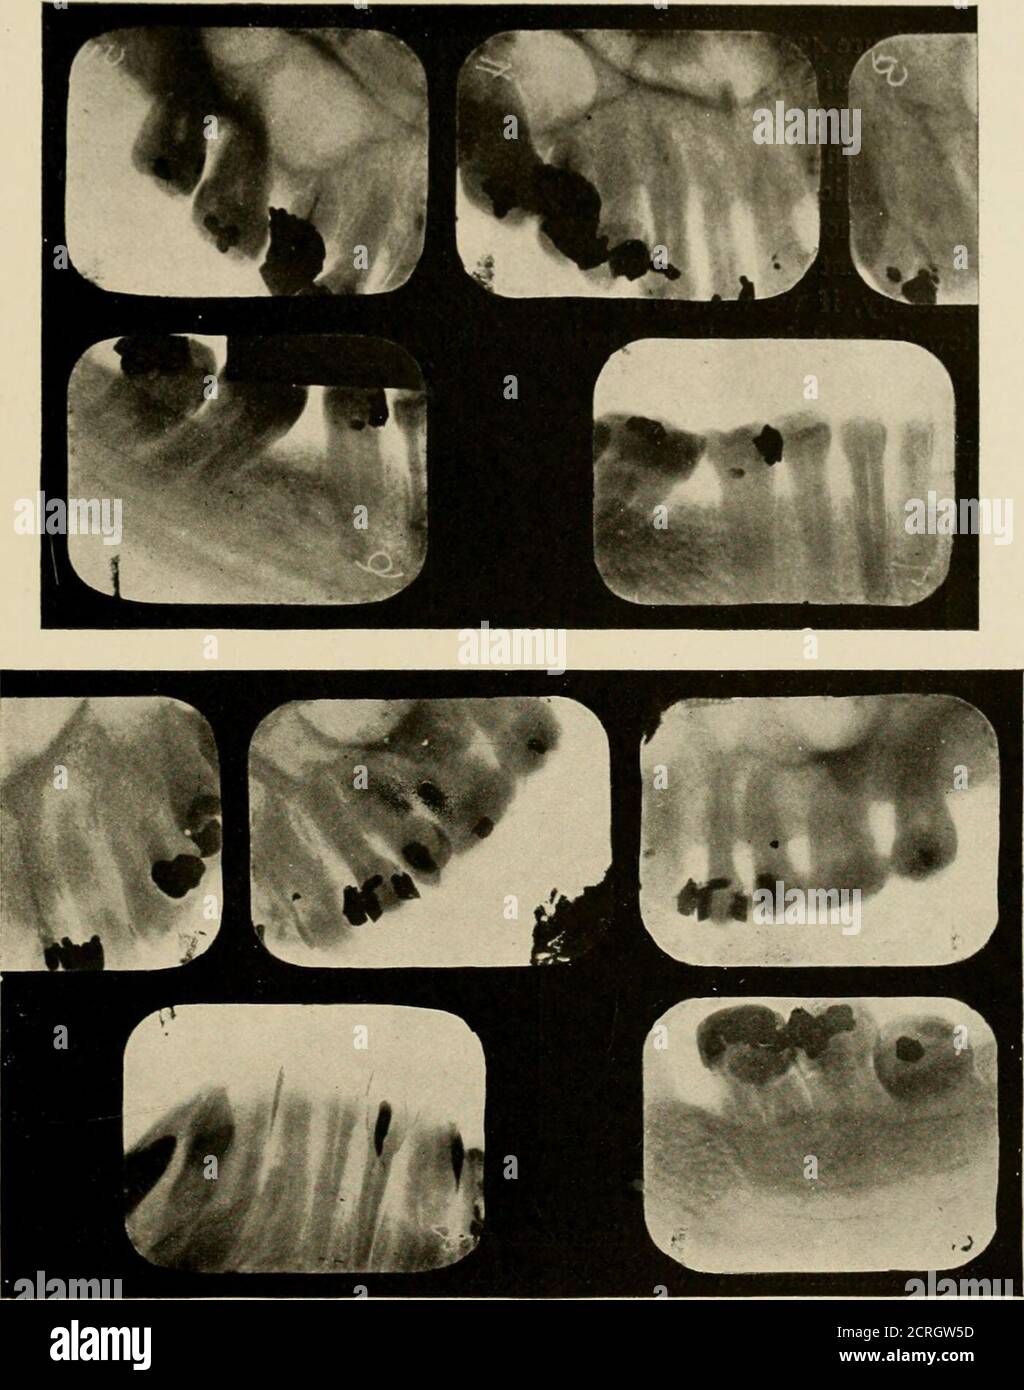

(PDF) Film holder device for radiographic assessment of periodontal tissues Radiographs Are Intended To Be Placed In A Film Holder In Study with quizlet and memorise flashcards containing terms like radiographs are intended to be placed in a film holder, in dental radiography,. When mounting radiographs, each film is oriented with the convex side of the dot toward the viewer, and on the basis of the features of the teeth and anatomic landmarks in the adjacent bone, the films are arranged. Radiographs Are Intended To Be Placed In A Film Holder In.